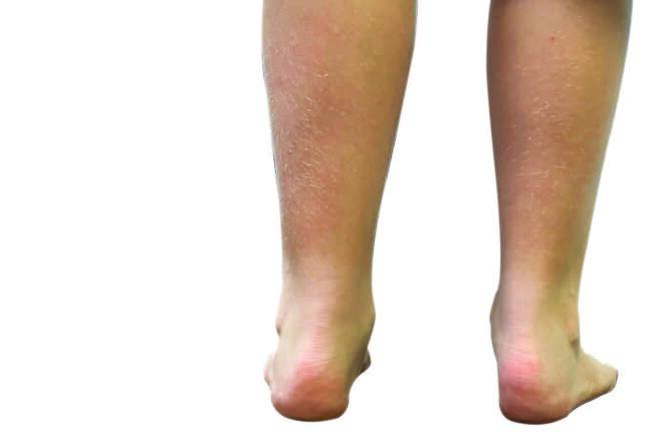

Evaluation of foot position and type is necessary as both a pronated and a supinated foot can lead to increased force on the calcaneal apophysis. In the findings of a pronated foot or pediatric flatfoot, pronation at the subtalar joint can lead to dorsiflexion of the calcaneus, possibly giving mechanical advantage to the Achilles tendon, as seen in the above-referenced equinus. When this occurs and the child begins to increase activity, the force on the posterior calcaneus can increase, thus leading to the Sever’s condition.

In a cavus or supinated foot type, tightness in the posterior complex may be intrinsic. Also, a lack of pronation in the midfoot may lead to a decrease in shock absorption and dispersion throughout the foot. This shock absorption then focuses on the posterior calcaneus, potentially leading to the patient’s chief concern.